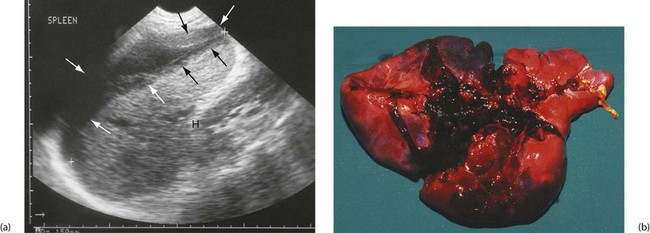

Closed abdominal injuries usually result from road traffic collisions, falls, sporting contact injuries and accidents involving horses. Following substantial blunt injury, about 20% will require laparotomy. The spleen is the most vulnerable organ, especially in left-sided injuries (see Fig. 15.7). Liver injury requires greater impact force, usually from the front or right side. Pancreatic and duodenal injuries are uncommon and usually result from a heavy central abdominal impact, transsecting the pancreas or retroperitoneal duodenum across the vertebral bodies. This most commonly occurs in children falling across the handlebars of bicycles. The kidneys are vulnerable to punches or kicks in the loins.

Spleen (Fig. 15.7): The spleen is the most commonly injured organ in blunt abdominal trauma. The organ should be preserved wherever possible because of the dangers of post-splenectomy infection and sepsis. In one study, 2.4% of all post-splenectomy patients suffered sepsis and more than 50% of those were fatal.

CT scanning enables accurate assessment and classification of the extent of injury. Haematomas and capsular tears not extending deeply can often be managed conservatively. More severe injuries are treated by urgent laparotomy and where possible, splenic repair (splenorrhaphy) by direct suture, fibrin glue or absorbable mesh bags. Segmental resection or splenic artery ligation can be done, but 50% of splenic substance must be preserved for useful function. Whenever splenic preserving techniques are employed, a period of careful observation for up to 10 days is required as catastrophic secondary haemorrhage can occur.